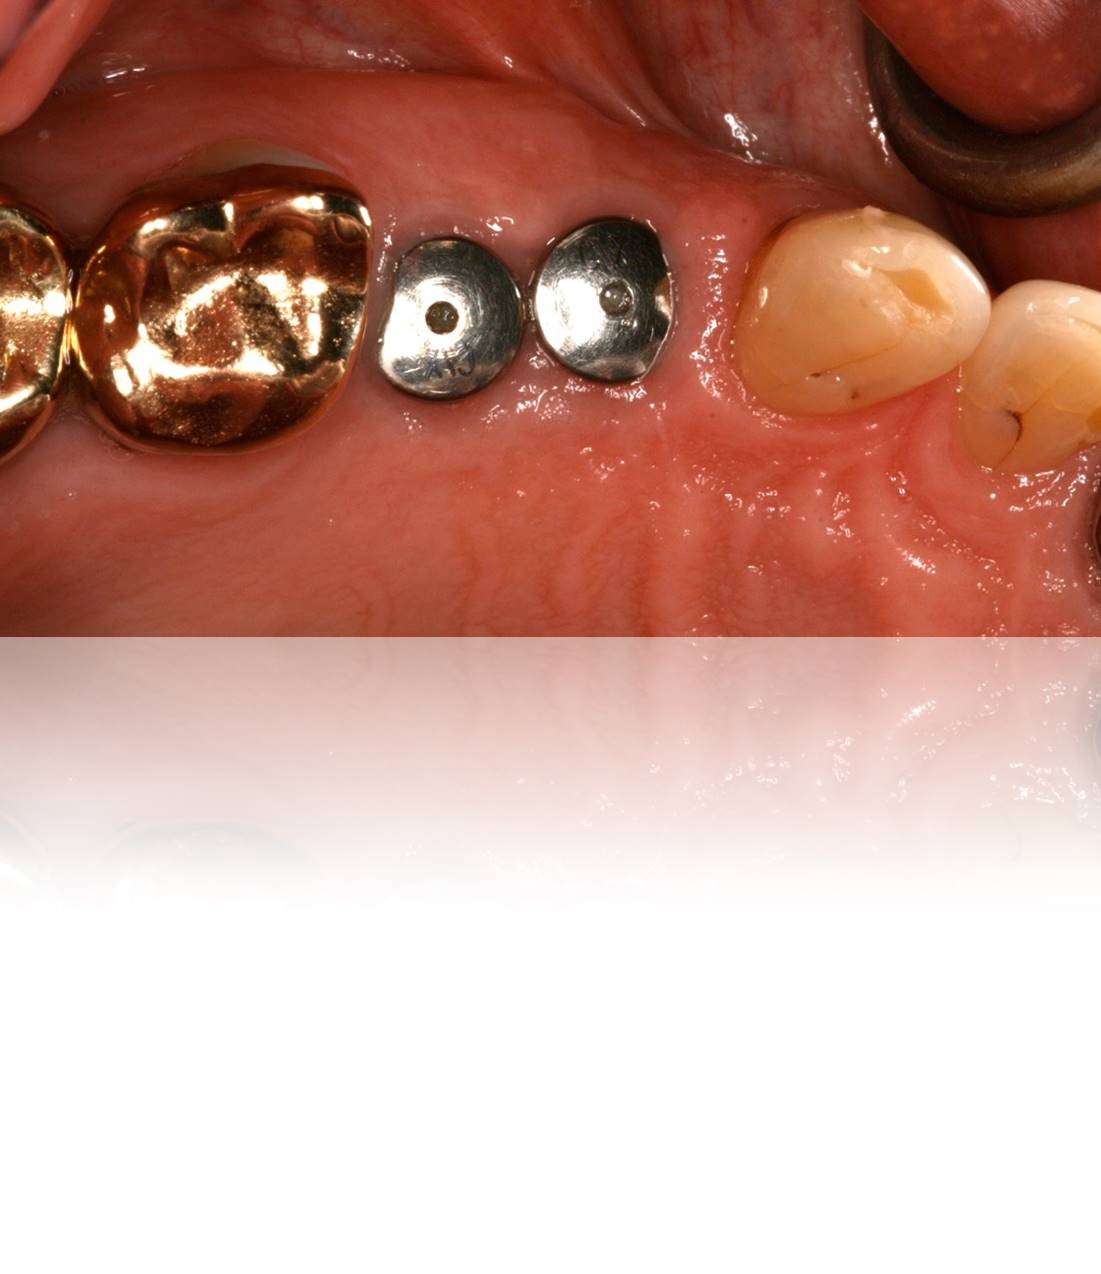

Figure 19. Close-up view of healing abutments in place for a patient who presented for implant restorations. Note this case was treated 4 years prior.

Figure 19

Figure 20. Upon removal of the healing caps, each site exhibited a deep sulcus, making “screwmentable” abutment/crown restorations ideal in order to avoid retentive cement subgingivally.

Figure 20